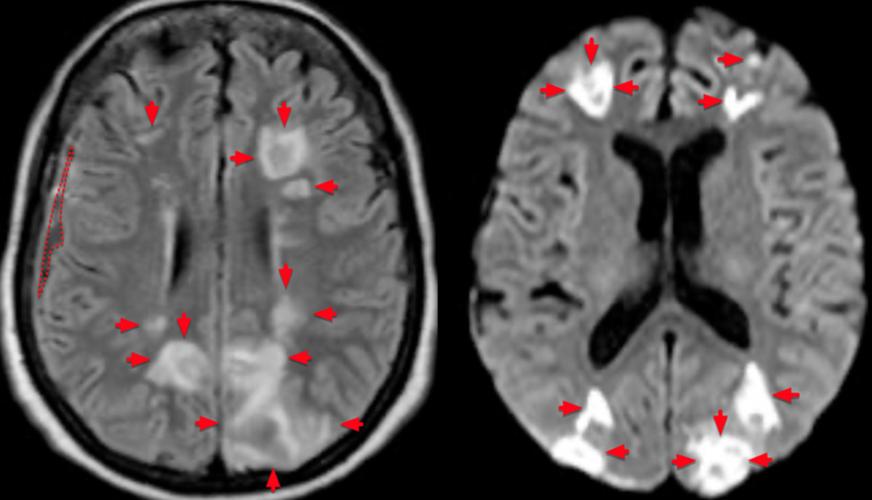

- DWI (弥散加权成像) + ADC (表观弥散系数图):急性脑梗的“金标准”,在发病数分钟内就能发现异常,DWI高信号+ADC低信号是急性梗死的典型表现。

- FLAIR表现:在超早期(<6小时),FLAIR上可能完全看不到异常,或者仅有非常轻微的信号改变,这是FLAIR的一个局限性,也是为什么医生在怀疑急性脑梗时,会加做DWI(弥散加权成像)序列的原因,DWI对早期细胞毒性水肿极其敏感,发病几分钟就能显示出高信号。